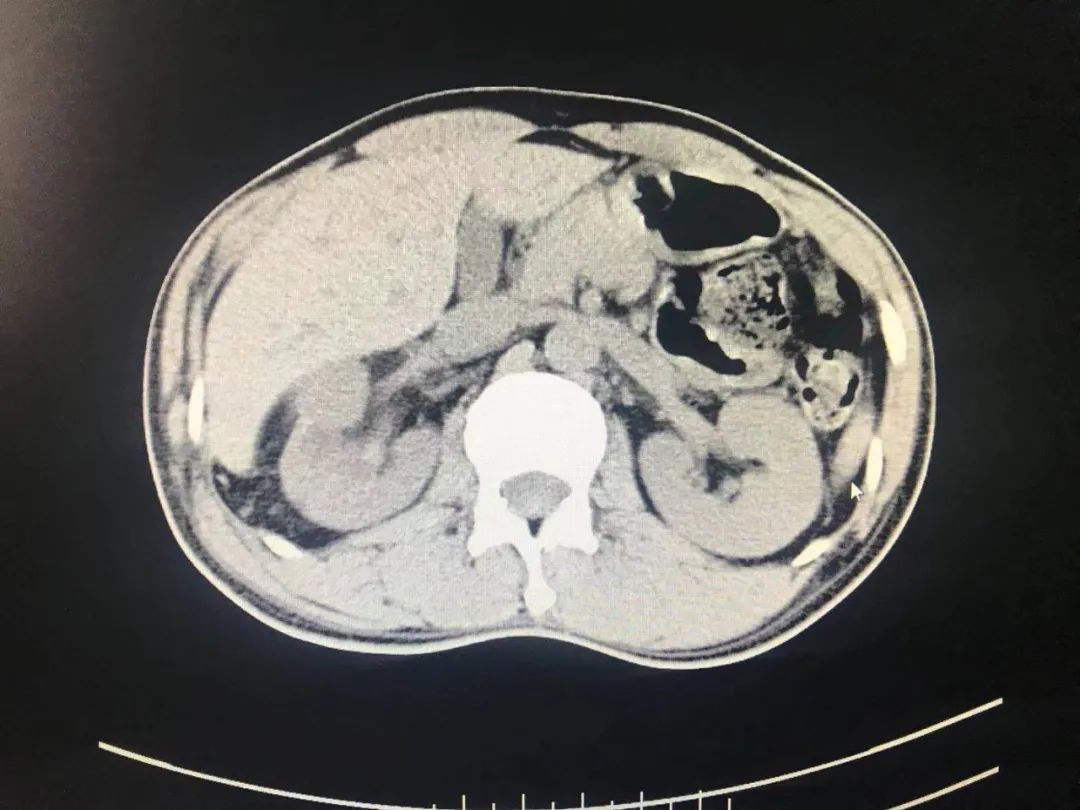

今年1月,医院外一科收治了一名40多岁的男性患者。该患者因腰部绞痛难忍,前来医院就诊。以刘文庭医生和尹曦医生为代表的外一科团队在对病人查体后发现,患者右肾结石散在且多发,结石密度影,肾实质厚,肾囊肿巨大且多发,手术难度颇大。

经过外一科医护团队对患者病情的仔细分析和详细论证,终于设计出一条适合患者病情的风险最小的手术治疗方案,即经皮肾囊肿输尿管软镜下右肾结石钬激光碎石术;利用此技术,将患者复杂性肾结石和肾囊肿通过同一通道经皮肾贯穿囊肿先内引流,再由内引流孔进入肾盂,最后利用钬激光进行碎石。患者利用此新技术前后共进行了两次碎石手术,手术治疗效果良好。第二次碎石手术顺利完成后,患者体内95%的结石碎石成功并成功排除体外,其病情已得到明显好转,目前已康复出院。